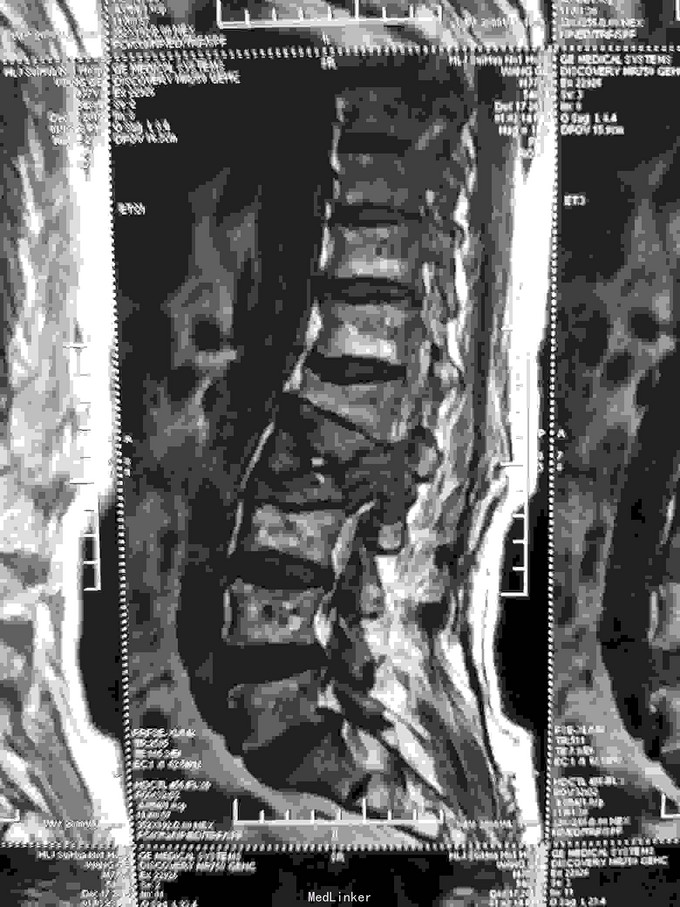

根据病史查体诊断:腰间盘突出症待确诊。应用消肿营养神经镇痛治疗。一天。查核磁共振示:腰椎多节段间盘突出伴椎管狭窄。第二腰椎骨破坏侵及椎板。部分突入椎管,脊髓受压。诊断:腰间盘突出伴椎管狭窄。第二腰椎转移癌,脊髓受压。经与家属沟通,查双肺CT:双肺下叶炎症。肺部纤维化。可见肿瘤阴影。肋骨及胸膜受累。胸椎部分骨破坏。最终诊断:双肺癌,胸椎,腰椎骨转移,脊髓受压。多节段腰椎间盘突出。病人至肿瘤科治疗。